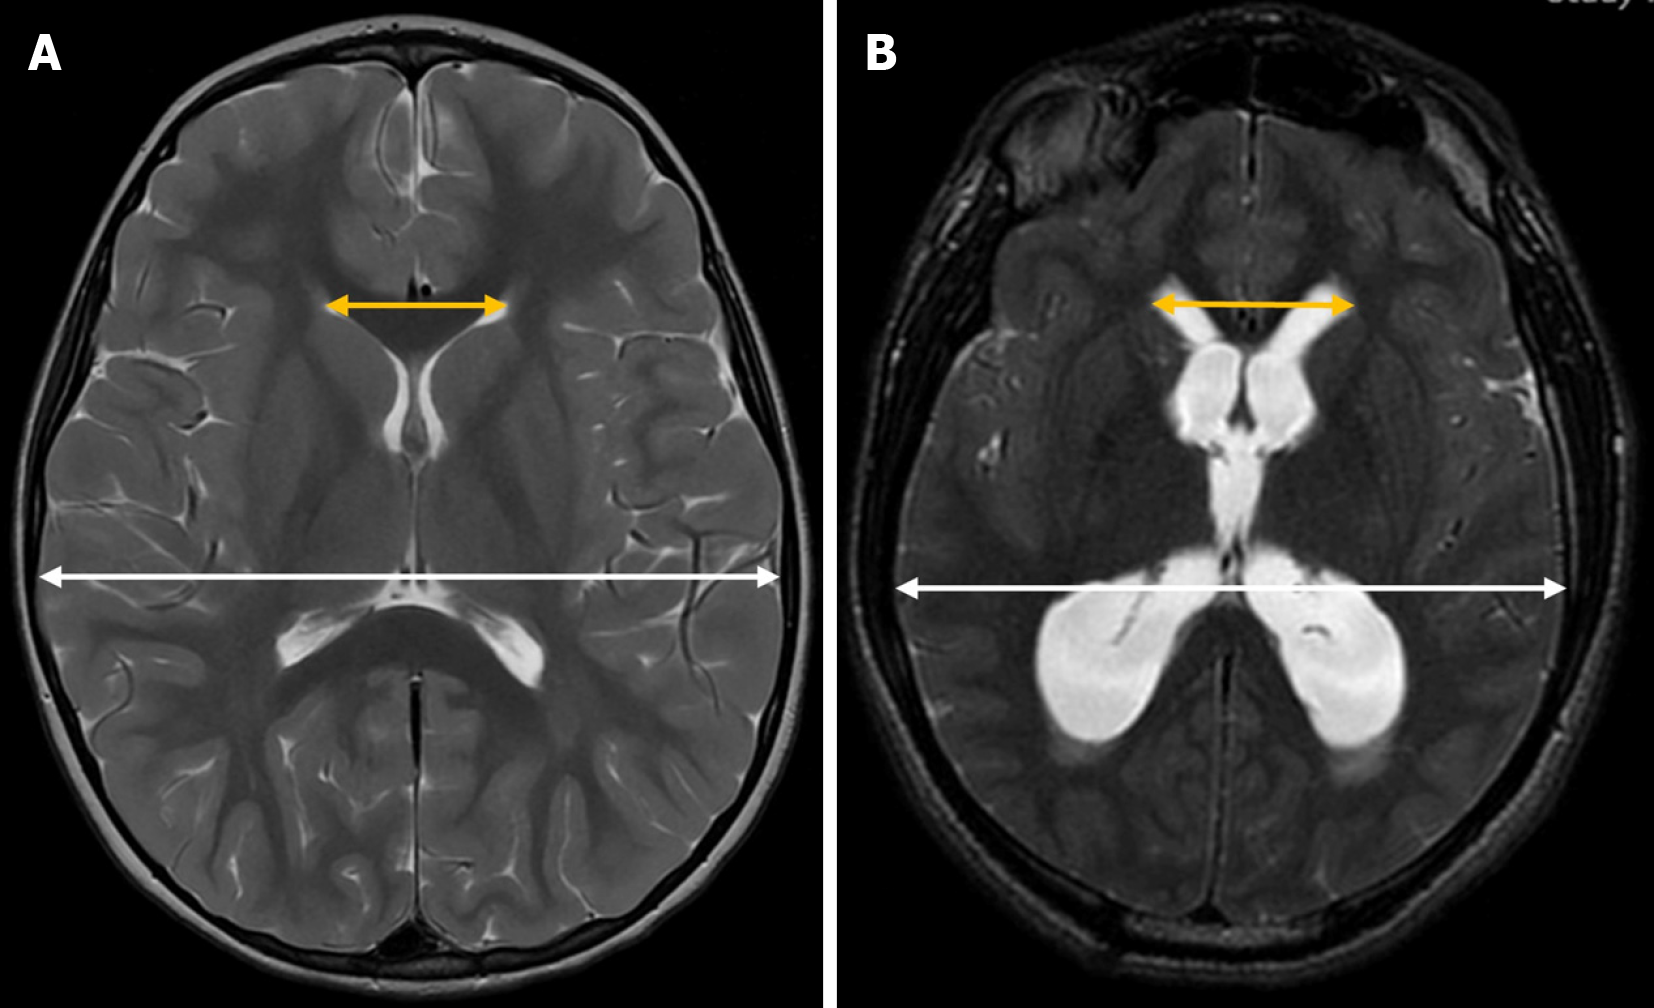

The anterior-posterior lateral ventricle diameter index is another quantitative measure used to assess lateral ventricle size. To calculate this index, an axial image must be reconstructed based on the anterior commissure-posterior commissure line (Figure 4). Once this plane is obtained, the most caudal axial slice that includes the entire body of the lateral ventricle, without including the thalami, is selected. In this slice, the maximum anteroposterior diameter of the lateral ventricle is measured and divided by the maximum intracranial anteroposterior diameter, measured along the falx cerebri.

This index has been used in adult populations, where a value greater than 0.5 is considered pathological[26,27]. Although its use has not yet been validated in pediatric patients, it holds potential as a useful biomarker for future applications.

The Bicaudate index is a neuroimaging tool used to assess the size of the frontal horns of the lateral ventricles in relation to the transverse diameter of the brain. To calculate this index, the distance between the most lateral portions of the frontal horns of the lateral ventricles at the level of the caudate nuclei is measured and then divided by the transverse brain diameter at the same level (along the same reference line used for ventricular measurements) in the axial plane on CT or MRI[33] (Figure 7).

There are no standardized reference values for this index. As with other ventricular indices, its application in transfontanellar ultrasound is technically challenging, limiting its use primarily to CT and MRI. Moreover, since it assumes ventricular symmetry, its diagnostic reliability decreases in cases of asymmetry or congenital ventricular malformations.